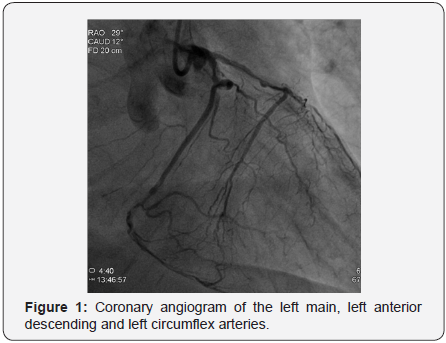

The patient was 87 years old male with a history of hypertension, type two diabetes mellitus presenting with shortness of breath progressively ending into respiratory distress over two days before admission to our department, the patient had a history of chronic kidney disease stage 3, serum creatinine was 1.68mg/dl on admission which became 2.23mg/dL thereafter, and positive Toponin I at admission, electrocardiogram showed sinus tachycardia with minimal ST depression at inferolateral leads, minimal ST segment elevation at V1-V4 with pathological Q waves, chest x-ray showed pulmonary edema, under impression of NSTEMI he was admitted and scheduled for an angiogram which showed severe triple vessel coronary artery disease with heavy calcifications of left system as illustrated in Figures 1 & 2; the proximal left anterior descending artery (LAD) had severe stenosis 93%, the mid left anterior descending artery (LAD) had chronic total occlusion (CTO) after giving a large septal branch and second diagonal (D2), collaterals to CTO segment from distal left circumflex artery (LCx) Grade 1/3; p-LAD bridging collaterals Grade 1/3 and large epicardial tortuous collateral from conus branch to distal LAD Grade 3/3, the proximal left circumflex artery (LCx) was acutely angled tortuous vessel with heavy calcifications showing proximal stenosis 74%, and the right coronary artery (RCA) was small non-dominant diffusely diseased vessel (Syntax score: 39.5), Echocardiogram showed borderline left ventricular performance with resting wall motion abnormalities, dyspnea then progressed, and acute respiratory distress developed that necessitated respiratory support with mechanical ventilation and hemodynamic support with intra-aortic balloon pump (IABP).